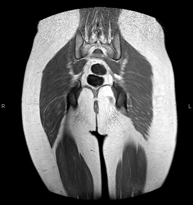

Prova diagnòstica no invasiva que consisteix en l'obtenció d'imatges d'alta definició anatòmica de la pelvis mitjançant l'ús d'un camp electromagnètic i ones de ràdio (amb un emissor i un receptor). No utilitza radiació ionitzant. Es realitza per a l'estudi de patologies d'úter, d'ovari, de trompes i de vagina, ja siguin d'origen tumoral, inflamatori o vascular. També permet valorar les estructures adjacents localitzades a la pelvis i la identificació de les seves alteracions. De vegades és necessari l'ús de contrast intravenós (Gadolini) per caracteritzar les lesions. - RM Pelvis masculina

Prova diagnòstica no invasiva que consisteix en l'obtenció d'imatges d'alta definició anatòmica de la pelvis masculina mitjançant l'ús d'un camp electromagnètic i ones de ràdio (amb un emissor i un receptor). No utilitza radiació ionitzant. No requereix preparació prèvia. En algunes ocasions necessita l'ús de contrast paramagnètic (Gadolini) per caracteritzar les lesions. Aquesta prova permet valorar òrgans com la bufeta urinària, la unió entre els urèters i la bufeta, la pròstata, les vesícules seminals, la uretra i els ossos de la pelvis, entre d'altres. - RM de Fetge